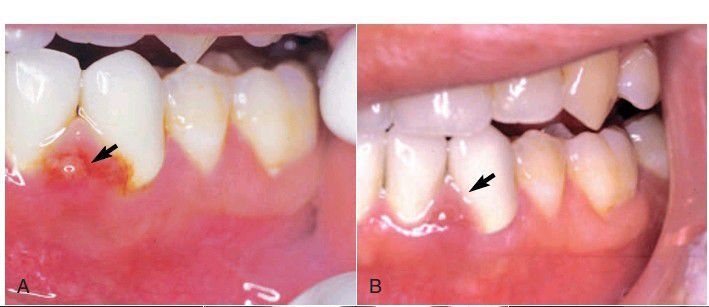

acute endodontic pathosis

Inflamed, edematous interproximal tissue (arrow) caused by acute endodontic pathosis. B, Soft tissue healing (arrow) 3 days after initiation of endodontic treatment.